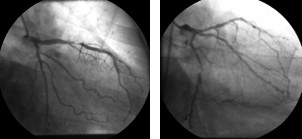

Ai fini della valutazione dell’entita’ della patologia coronarica, si parla di stenosi significativa quando si ha una stenosi coronarica superiore o uguale al 70%, se i vasi coronarici sono la discendente anteriore, la circonflessa, e la coronaria destra, se si tratta del tronco comune allora la stenosi deve essere superiore al 50%.

Stenosi ramo discendente anteriore e stenosi ramo circonflesso